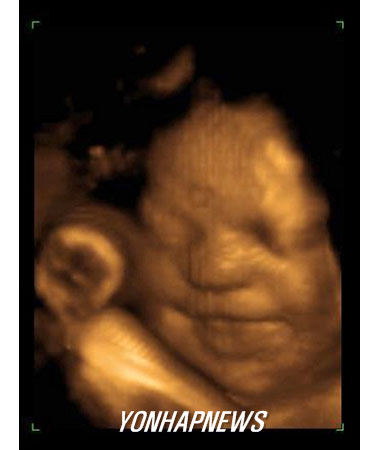

임신 3기 태아, 낮은 소음 가해지면 ''우는 행동''보여

(자료사진/연합사진)

아기가 첫 울음을 터뜨리는 것은 병원 분만실이 아니라 엄마의 자궁 속인 것으로 보인다고 뉴질랜드 과학자들이 보고했다.

오클랜드대학의 에드 미첼 박사 등 연구진은 비디오 초음파 영상을 통해 임신 3기의 태아들을 관찰한 결과 엄마의 배에 낮은 수준의 소음이 가해지면 이에 대한 반응으로 "우는 행동"을 보였다고 밝혔다.

33주 된 태아를 대상으로 한 관찰에서 태아는 위장이 꾸르륵거리는 것과 비슷한 소음과 진동이 엄마 배에 가해지자 ''깜짝 놀라는'' 반응을 보이더니 심호흡을 하고 입을 벌리며 턱을 떠는 등 울음과 관련된 행동을 하는 것으로 나타났다.